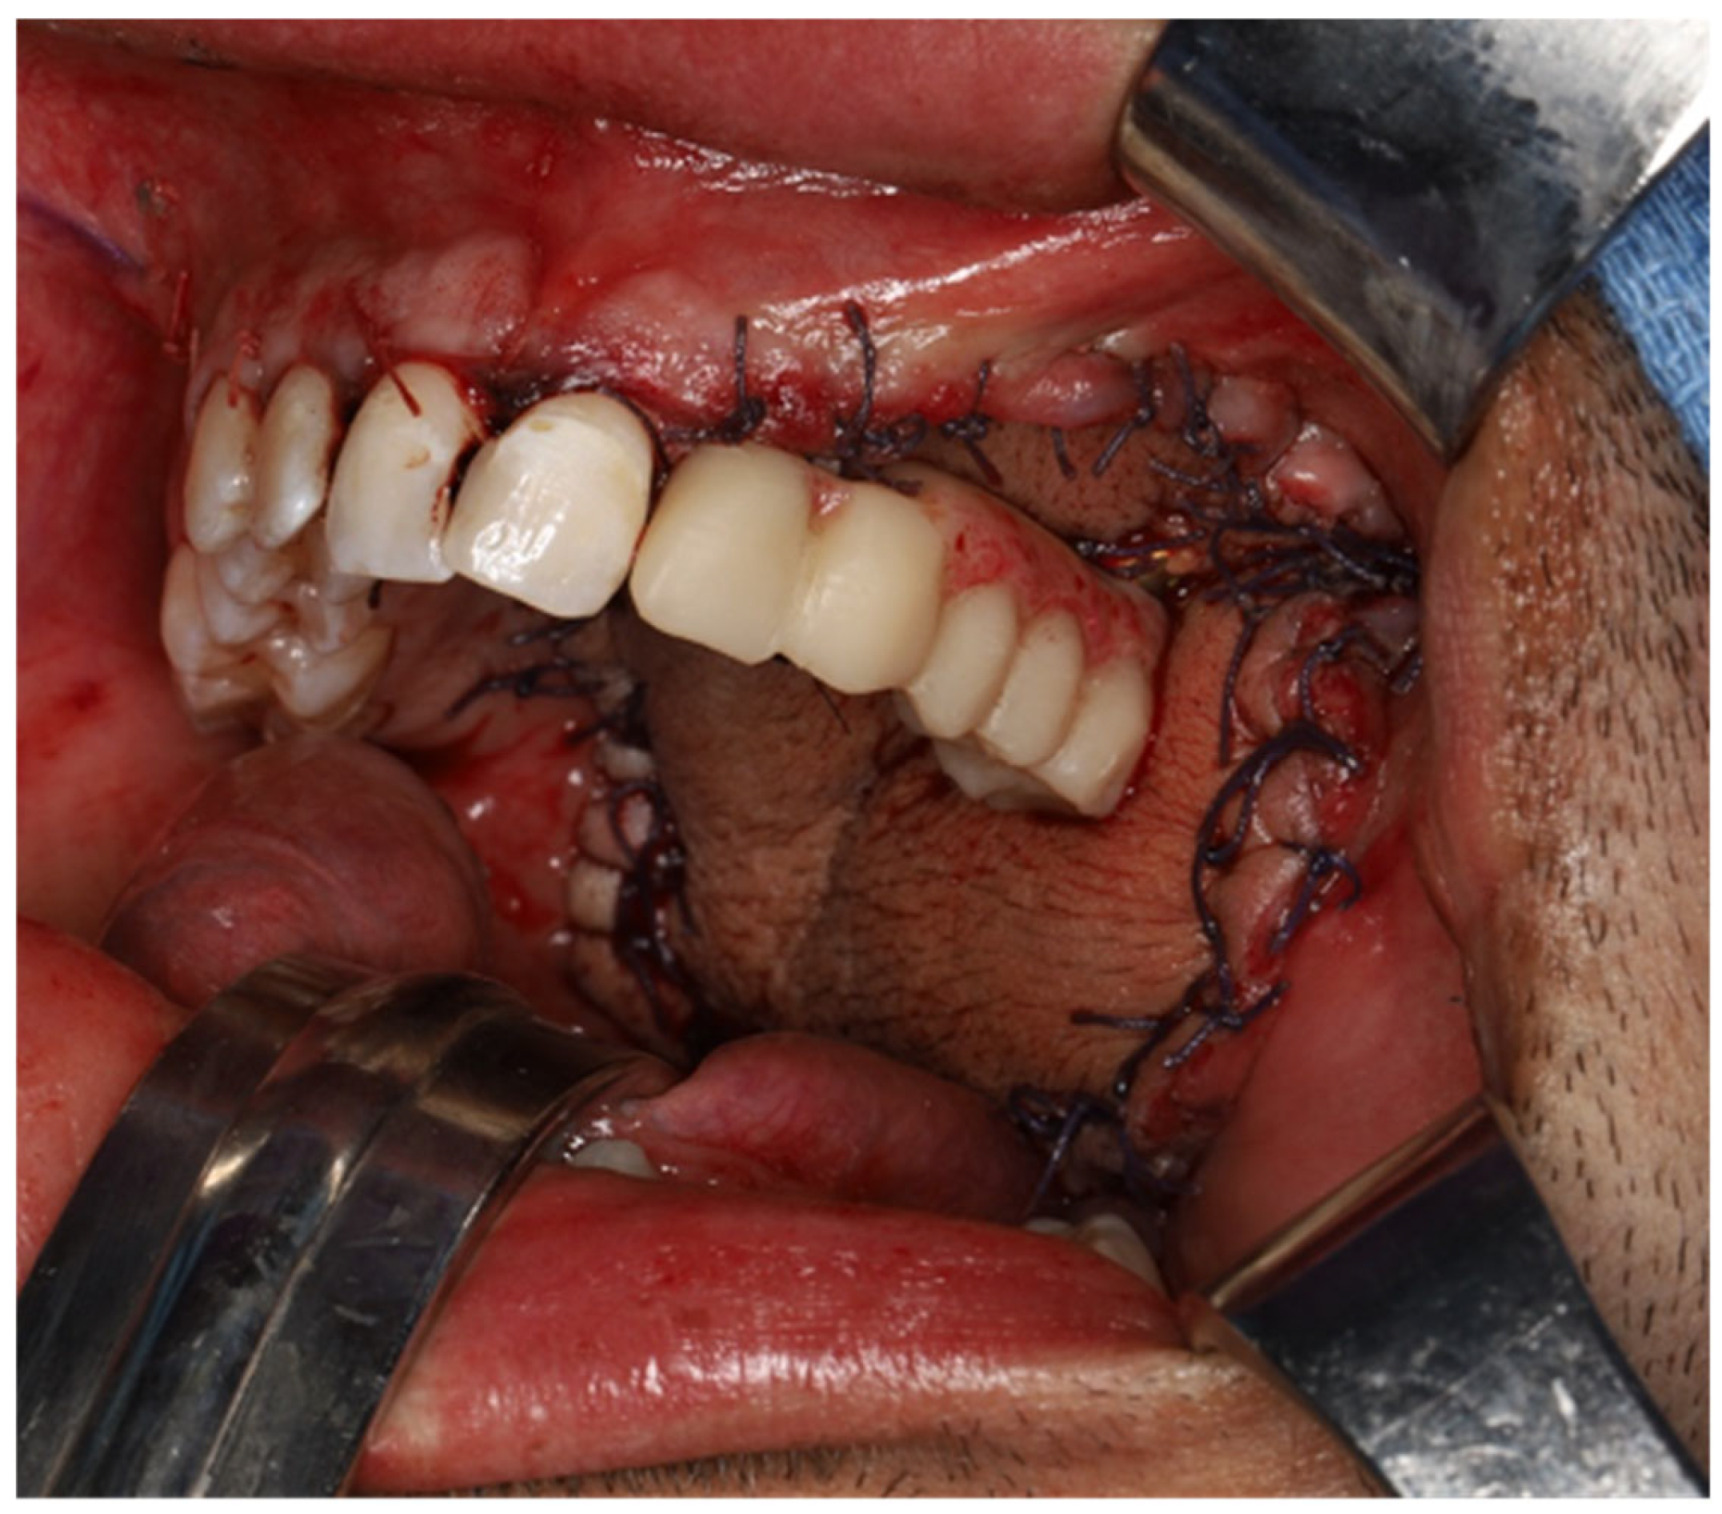

- Flap Perforation: Create a stab incision with a #11 blade and gently dilate with fine Mosquito forceps. Avoid over-enlarging the perforation, maintaining soft tissue tension to allow abutment insertion while preventing outward displacement. Use sutures as needed to reinforce tissue tension around the abutment.

- Immediate restoration: Following free flap anastomosis, the prosthodontic team can proceed with immediate dental restoration. This restoration can be planned using CAD-CAM, based on the planned zygomatic implants, abutment emergence, and the patient’s occlusion.